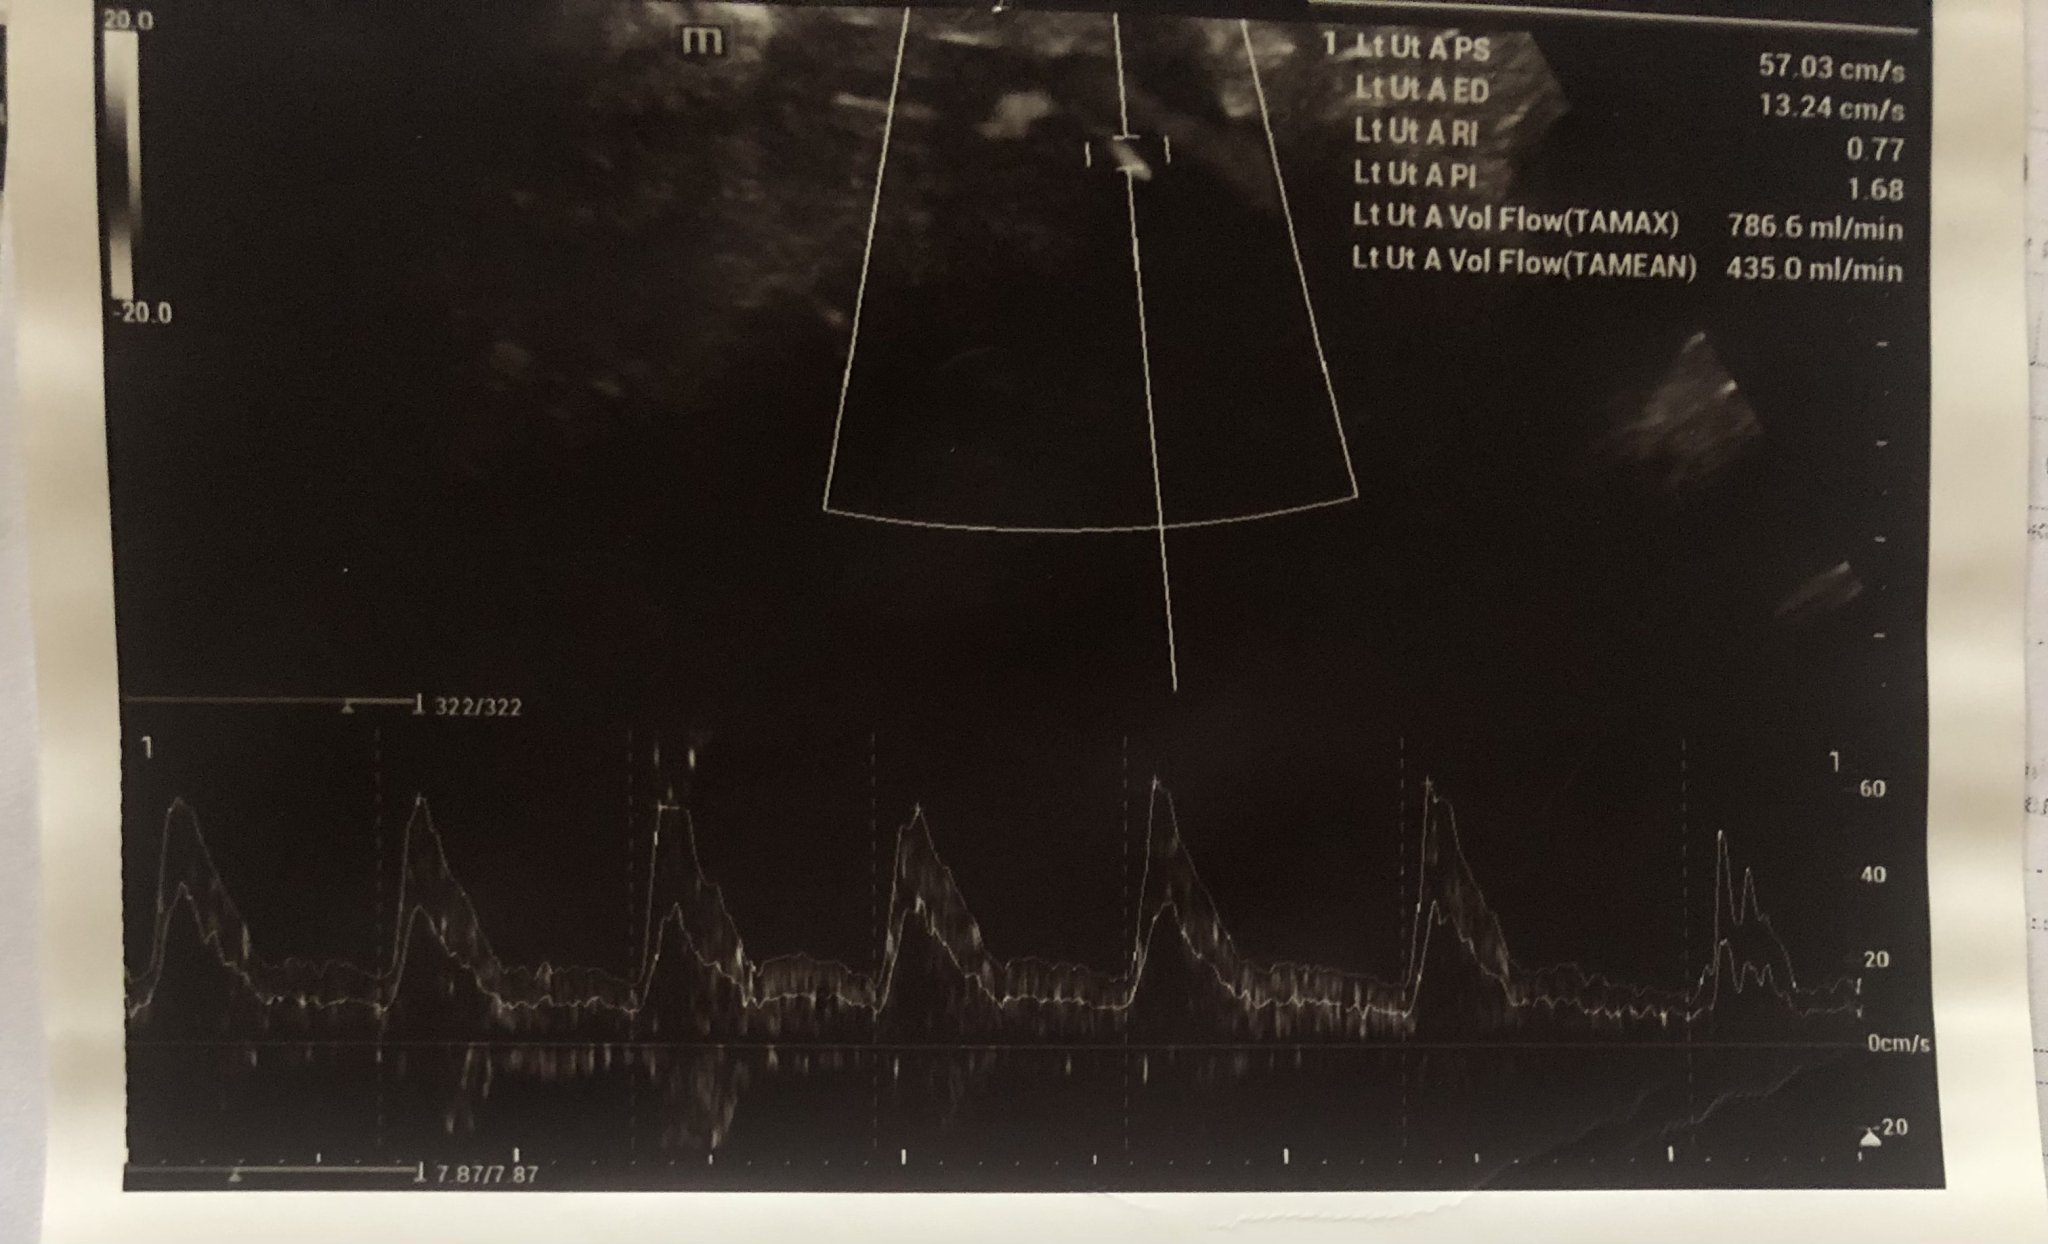

Ето така изглежда снимка от доплер на лява и дясна страна на маточна артерия, стойностите са описани отстрани като RI и PI. Освен това трябва да има и снимка от измерване на кръвотока към пъпната връв, който се означава на снимката (ако не се лъжа) като Umb A PI, съответно Umb A RI.

Мики, до колкото при мен проблемна е стойността на PI от 1,68. (В петък измерена в Токуда 1,59) мисля, че си супер.

Интересно, в моята ФМ пише само маточта артерия PI 1.38 еквивалент на 0.890MoM